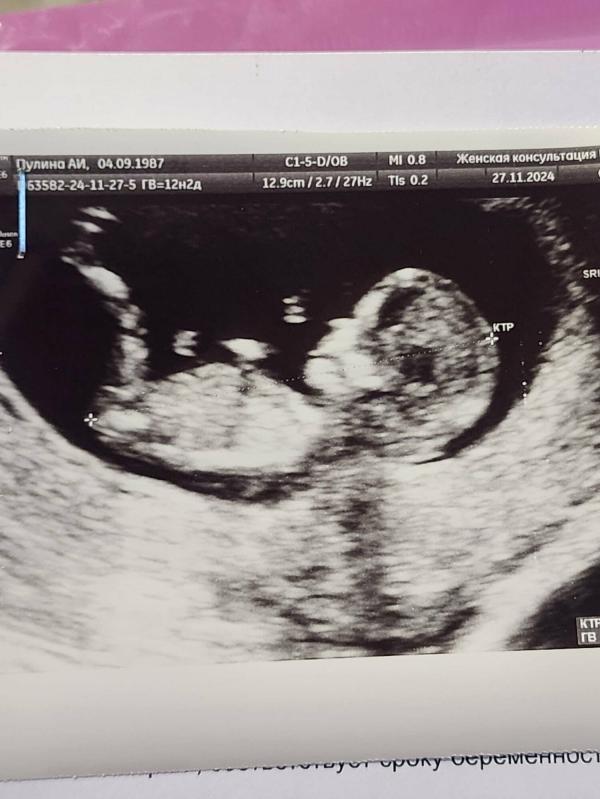

Дали на УЗИ фото, виден половой бугорок. Есть знатоки? Принимаю варианты😀😀

По половому бугорку не каждый узист определяет, только хороший профессионал. Зато девочки в МЛ сходу